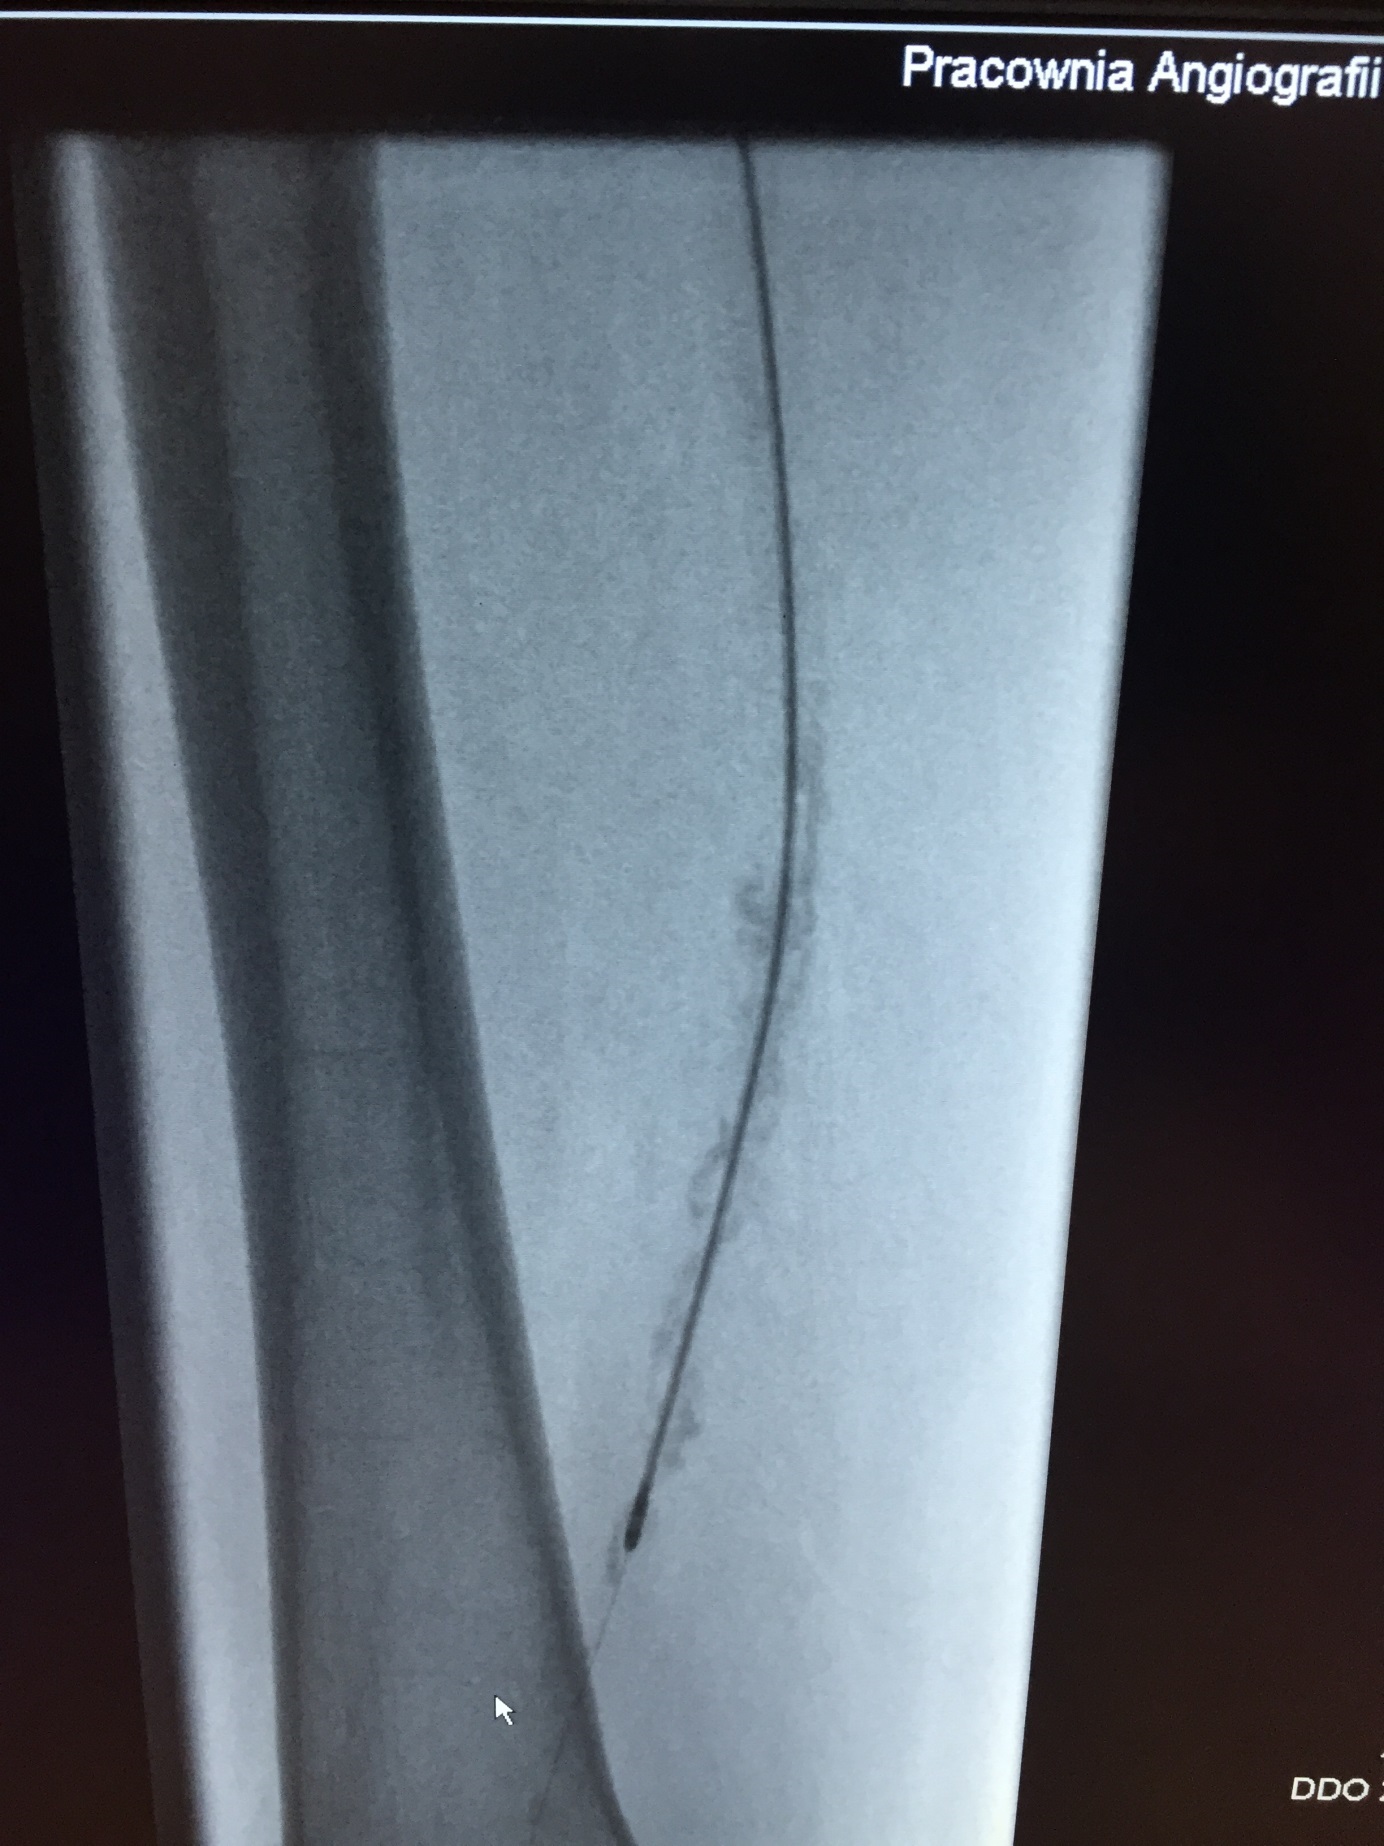

Zespół Kliniki Chorób Naczyń i Chorób Wewnętrznych Szpitala Uniwersyteckiego nr 2 im dr. J. Biziela wprowadził nową technikę udrażniania naczyń. W Pracowni Angiografii i Diagnostyki Inwazyjnej (Radiologii Zabiegowej) lekarze wykonali kilka zabiegów wewnątrznaczyniowych z użyciem aterektomu-JetStream, urządzenia, które drogą przezskórną (wewnątrznaczyniową) umożliwia rozdrobnienie blaszek miażdżycowych i skrzeplin w tętnicach różnego kalibru za pomocą obrotowej turbinki, a następnie odessanie ściętego materiału przez mechanizm próżniowy i jego usunięcie poza organizm.